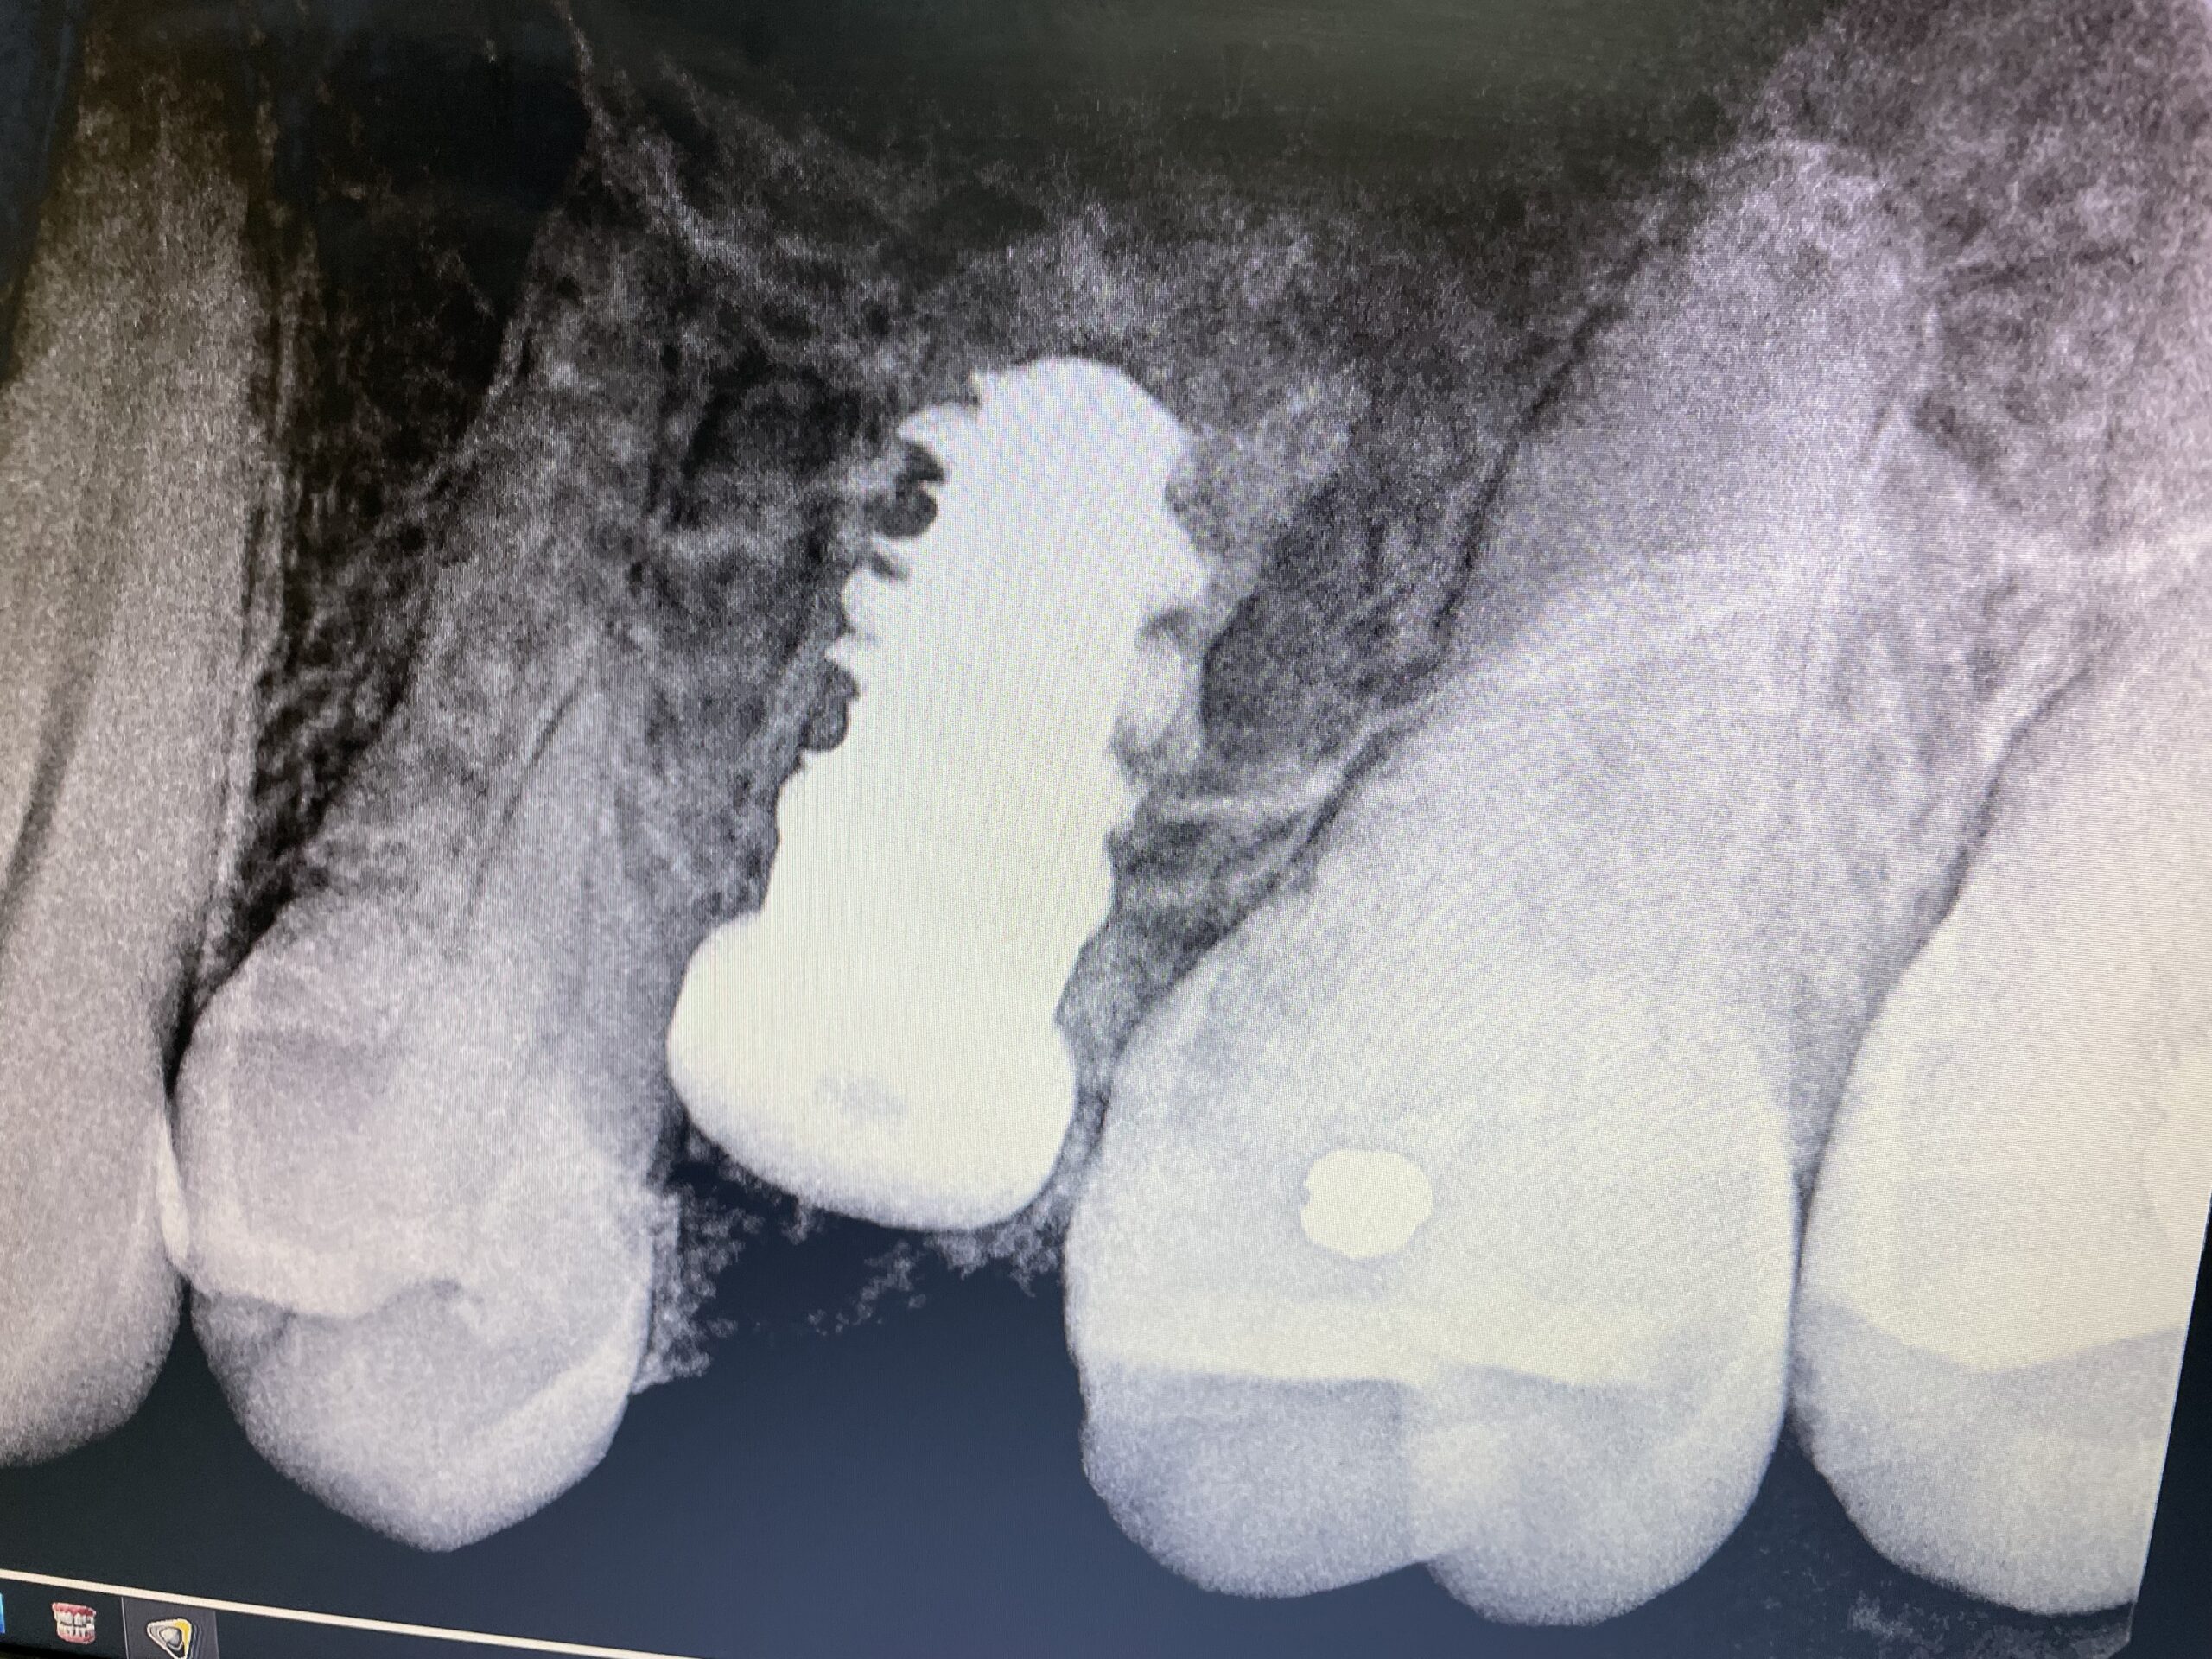

Titanium Screw in your Skull

- Price: £1950

- From: The Dentist (not NHS)

Charlie says… As the owner of several titanium frames and even some handmade Moonmen Ti riser bars, I am familiar with paying out for titanium. However, this one beats them all when evaluated on a fun:cost ratio basis. At only 5mm wide and £1,950 it is by far the costliest bit of Ti in my life, whilst also being zero fun. Actually, that is not true, it was negative fun. When they drill into your skull the noise is incredible. You can’t feel anything, but a reverberating skull sounds amazing, but not in a good way. In about another £1,000 or so a fake tooth will fill this gap.

On the plus side I am now conditioned to view any titanium bicycle product as absolutely excellent value for money.